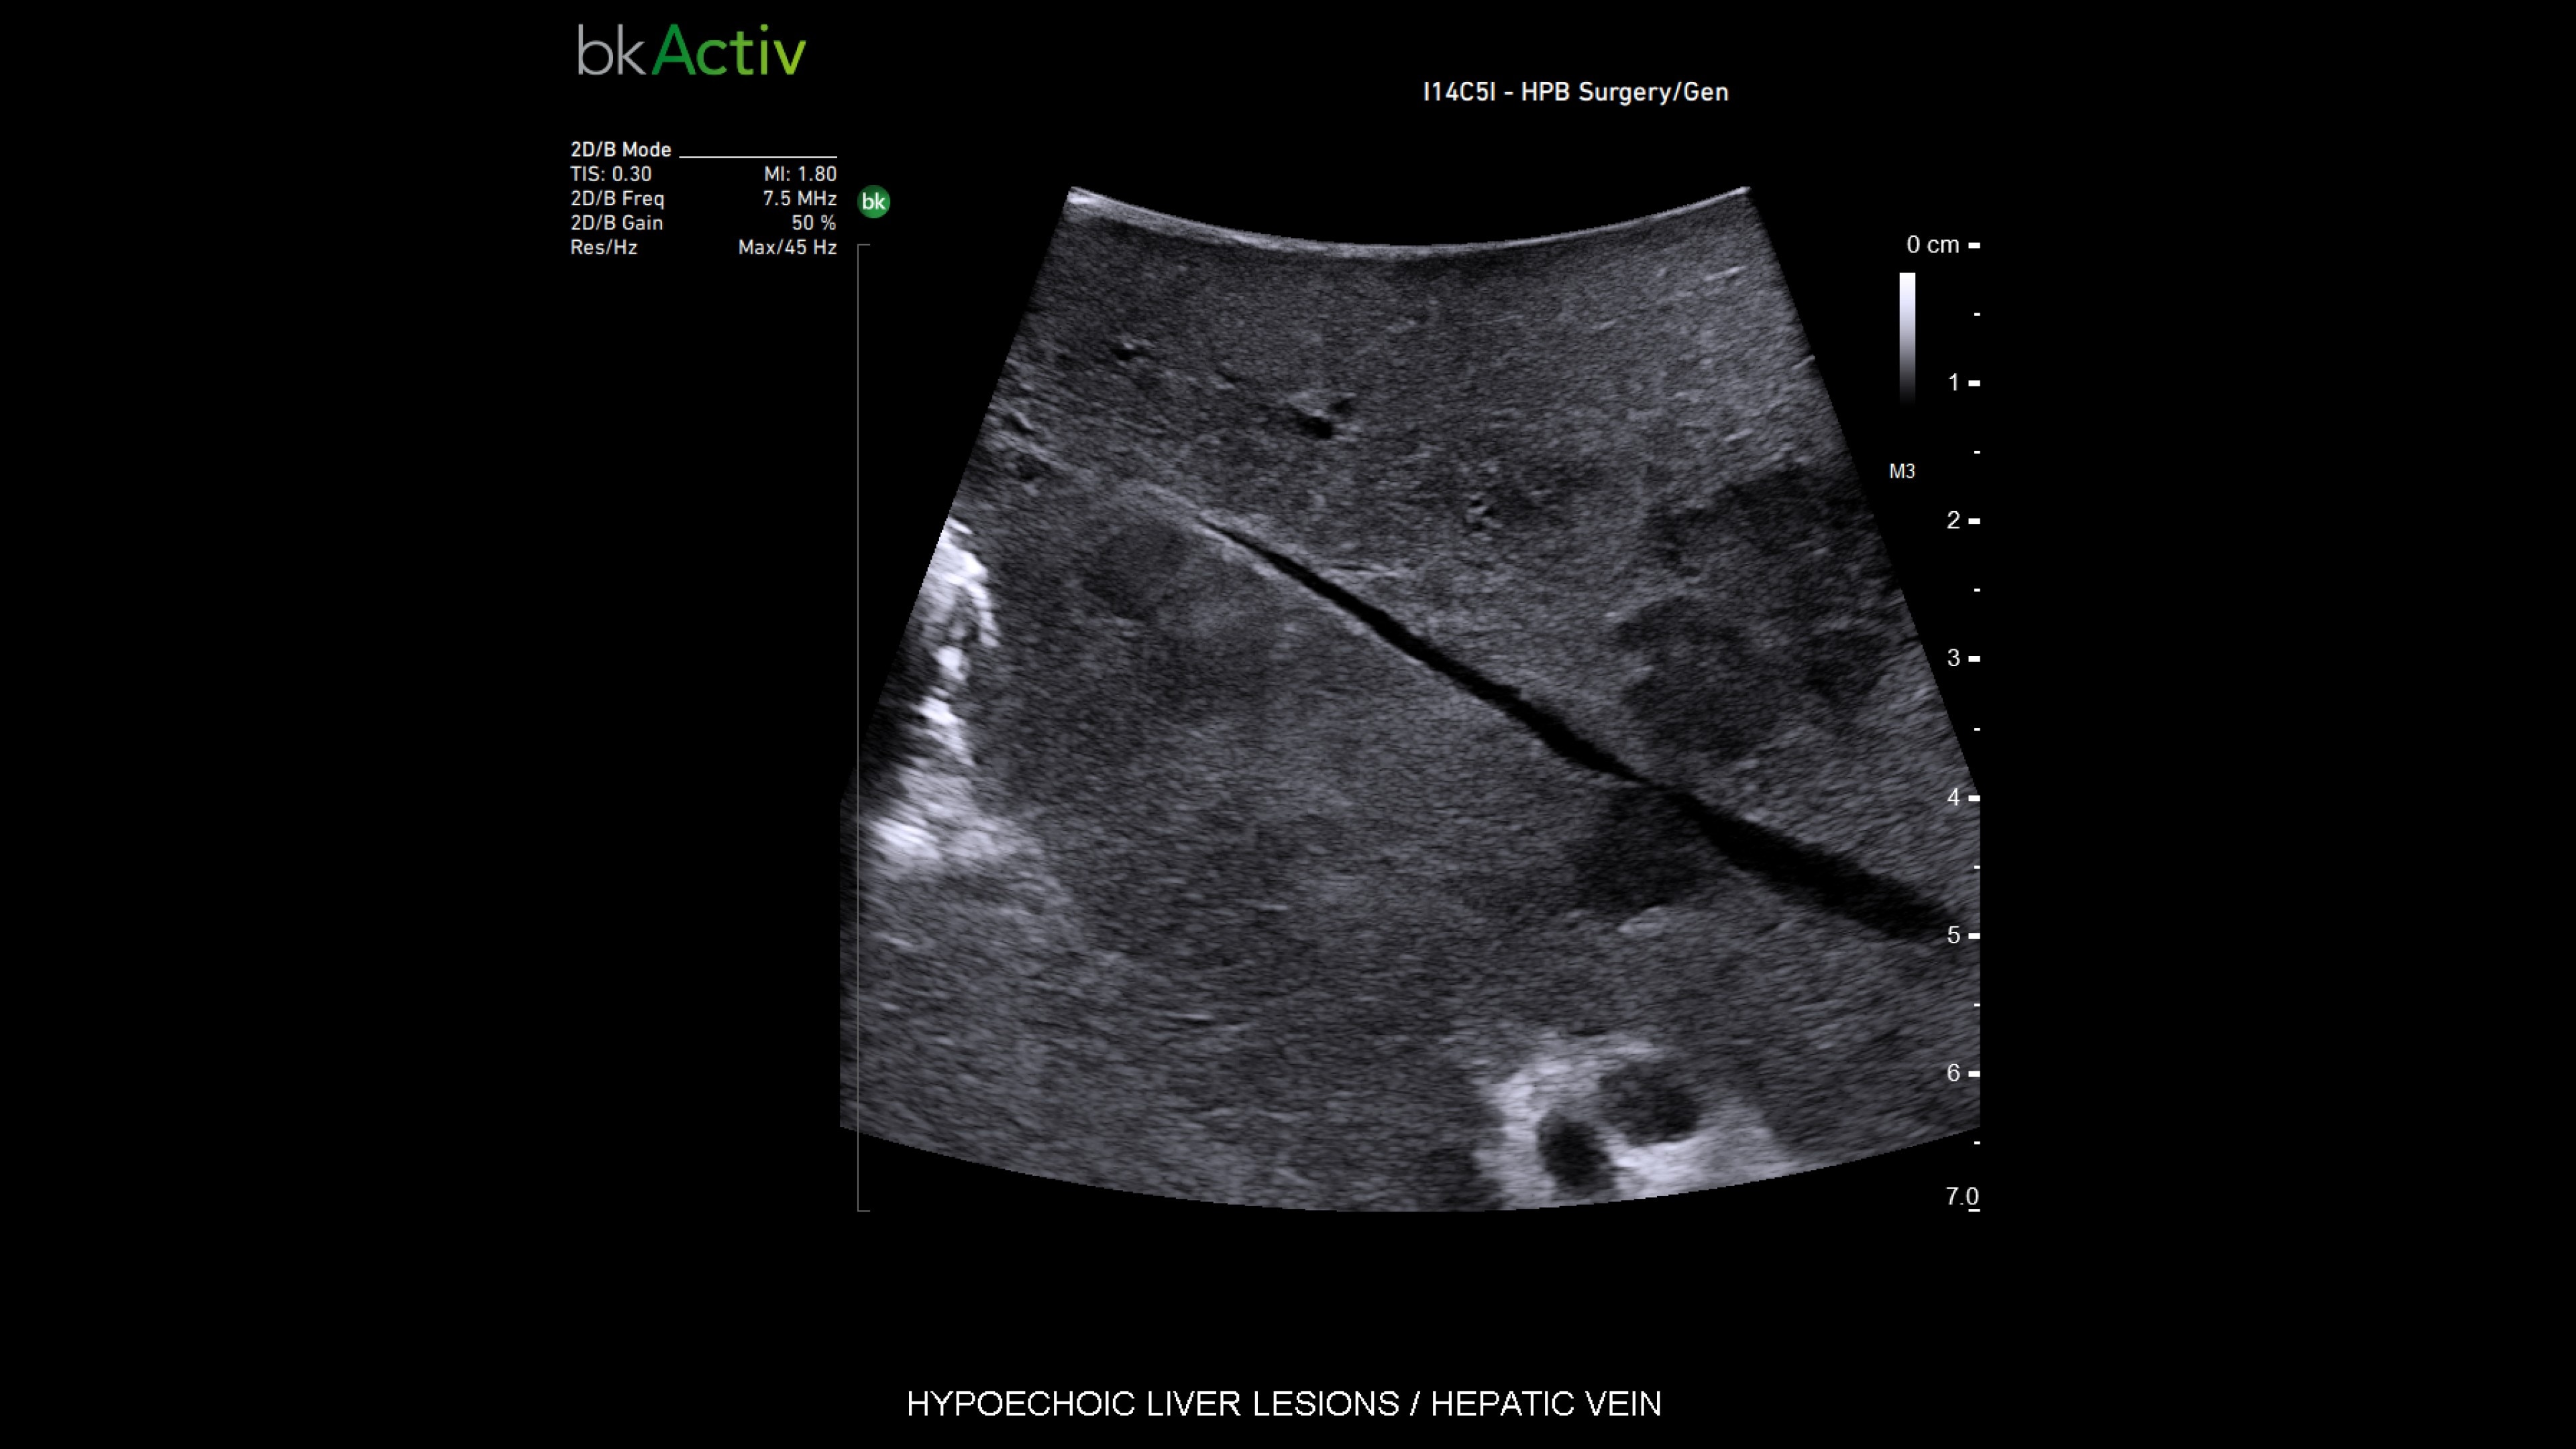

Active imaging with real-time intraoperative ultrasound supports fast imaging of the biliary system and is non-radiating, helping you reduce radiation hazards to your patients and staff.

Imaging to guide cholecystectomies

Discover the clinical benefits of active imaging with intraoperative ultrasound for laparoscopic cholecystectomy procedures. Using bkActiv and the Advanced Laparoscopic Transducer, surgeons can visualize anatomy and monitor progress as many times as needed during the procedure.

iUS is beneficial for cholecystectomies due to its safety, quick and repeatable imaging capabilities and ability to detect choledocholithiasis and enable visualization of biliary tract anatomy.

• iUS has minimal safety risks as it is non-irradiating and does not required cannulation. ¹⁻³

• iUS can be used dynamically throughout dissection adding minimal time to a cholecystectomy procedure. iUS can also repeated, helping to assess common bile duct integrity at the end of the procedure.¹⁻⁵

• iUS helps differentiate between sludge, stone, polyps, cysts, and tumors when determining if there is a presence of gallstones in the common bile duct.⁵,⁶

• iUS uses color flow doppler to help differentiate between vessels and ducts and is overall effective at imaging difficult cases such as inflammation or fibrosis .¹,⁴⁻⁶